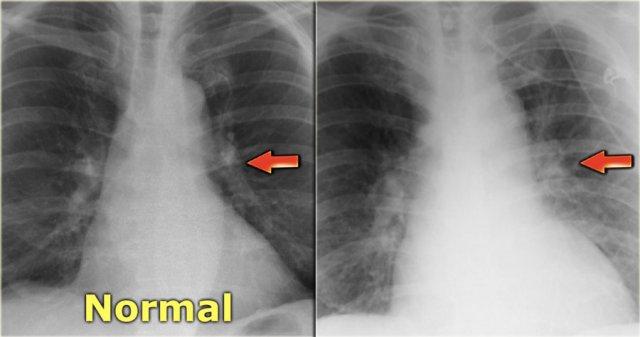

Hình ảnh các mạch máu thùy trên của bệnh nhân trong tình trạng bình thường (trái) và trong giai đoạn suy tim sung huyết (phải). Lưu ý độ rộng tăng lên của cuống mạch máu (mũi tên đỏ).

Trên phim X-quang ngực bình thường với bệnh nhân đứng thẳng, các mạch máu phổi cấp máu cho vùng phổi trên có kích thước nhỏ hơn và số lượng ít hơn so với các mạch cấp máu cho nền phổi.

Tỷ lệ động mạch/phế quản

Bình thường, các mạch máu ở thùy trên nhỏ hơn phế quản đi kèm với tỷ lệ là 0,85 (3).

Ở mức rốn phổi, chúng có kích thước tương đương nhau, và ở thùy dưới, các động mạch lớn hơn với tỷ lệ là 1,35.

Khi có sự tái phân phối lưu lượng máu phổi, tỷ lệ động mạch/phế quản sẽ tăng lên ở các thùy trên và thùy giữa.

Điều này thể hiện rõ nhất ở vùng quanh rốn phổi.

Bên trái là hình ảnh bệnh nhân có tim to và tái phân phối.

Các mạch máu thùy trên có đường kính > 3 mm (bình thường 1-2 mm).

Lưu ý tỷ lệ động mạch/phế quản tăng ở mức rốn phổi (mũi tên).

Phim cũ để so sánh (trái) Suy tim sung huyết với tái phân phối tuần hoàn, phù mô kẽ và một ít dịch màng phổi

Hình bên trái là bệnh nhân suy tim sung huyết.

Kích thước tim tăng so với phim cũ.

Các dấu hiệu khác của suy tim sung huyết cũng hiện diện, bao gồm tái phân phối tuần hoàn phổi, phù mô kẽ và một ít dịch màng phổi.